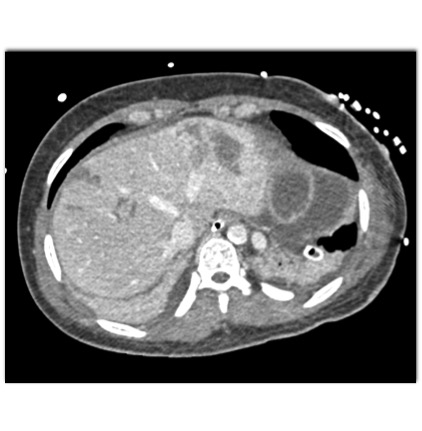

In this patient the most likely diagnosis for the new liver lesions is?

liver abscess

liver infarcts

metastases to the liver

focal fatty infiltration